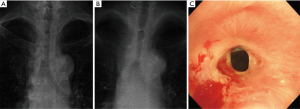

There were differences in stent detection ability depending on the location: trachea, RMB and RBI, and LMB. In the LMB, DTS had the best ability to detect stents, with a sensitivity of 98.7% (95% CI, 93.1–100.0%). The sensitivity of DTS in detecting stents located in the trachea was the lowest at 85.9% (95% CI, 75.0–93.4%) (Table 2, Figure 1A).

Diagnostic performance for the detection of silicone stent-related complications

Of the 213 cases, 53 (53/213, 24.9%) showed stent migration. The ability of DTS to detect stent migration was higher than that of CXR. For stent migration, the sensitivities of DTS and CXR was 45.3% (95% CI, 31.6–59.6%) and 24.5% (95% CI, 13.8–38.3%) (P=0.025) (Figure 1B). The accuracies of DTS and CXR were 84.0% (95% CI, 78.4–88.7%) and 80.8% (74.8–85.8%) (P=0.396).

Of the total 213 cases, 121 (121/213, 56.8%) cases of stent obstruction were caused by granulation tissue or fibrosis. The ability of DTS to detect granulation tissue or fibrosis at the end of the stent was significantly better than that of CXR (Figure 1B). The sensitivity of DTS was 64.5% (95% CI, 55.3–73.0%), specificity was 85.9% (95% CI, 77.1–92.3%), and accuracy was 73.7% (95% CI, 67.3–79.5%). For CXR, the sensitivity was 19.0% (95% CI, 12.5–27.1%), specificity was 100.0% (95% CI, 96.1–100.0%), and accuracy was 54.0% (95% CI, 47.1–60.8%) (Table 3). As shown in Figure 2, granulation tissue grew on the distal end of the LMB stent and caused a partial obstruction. As shown in Figure 3, fibrosis occurred at the end of the mid-tracheal stent, creating an airway obstruction.